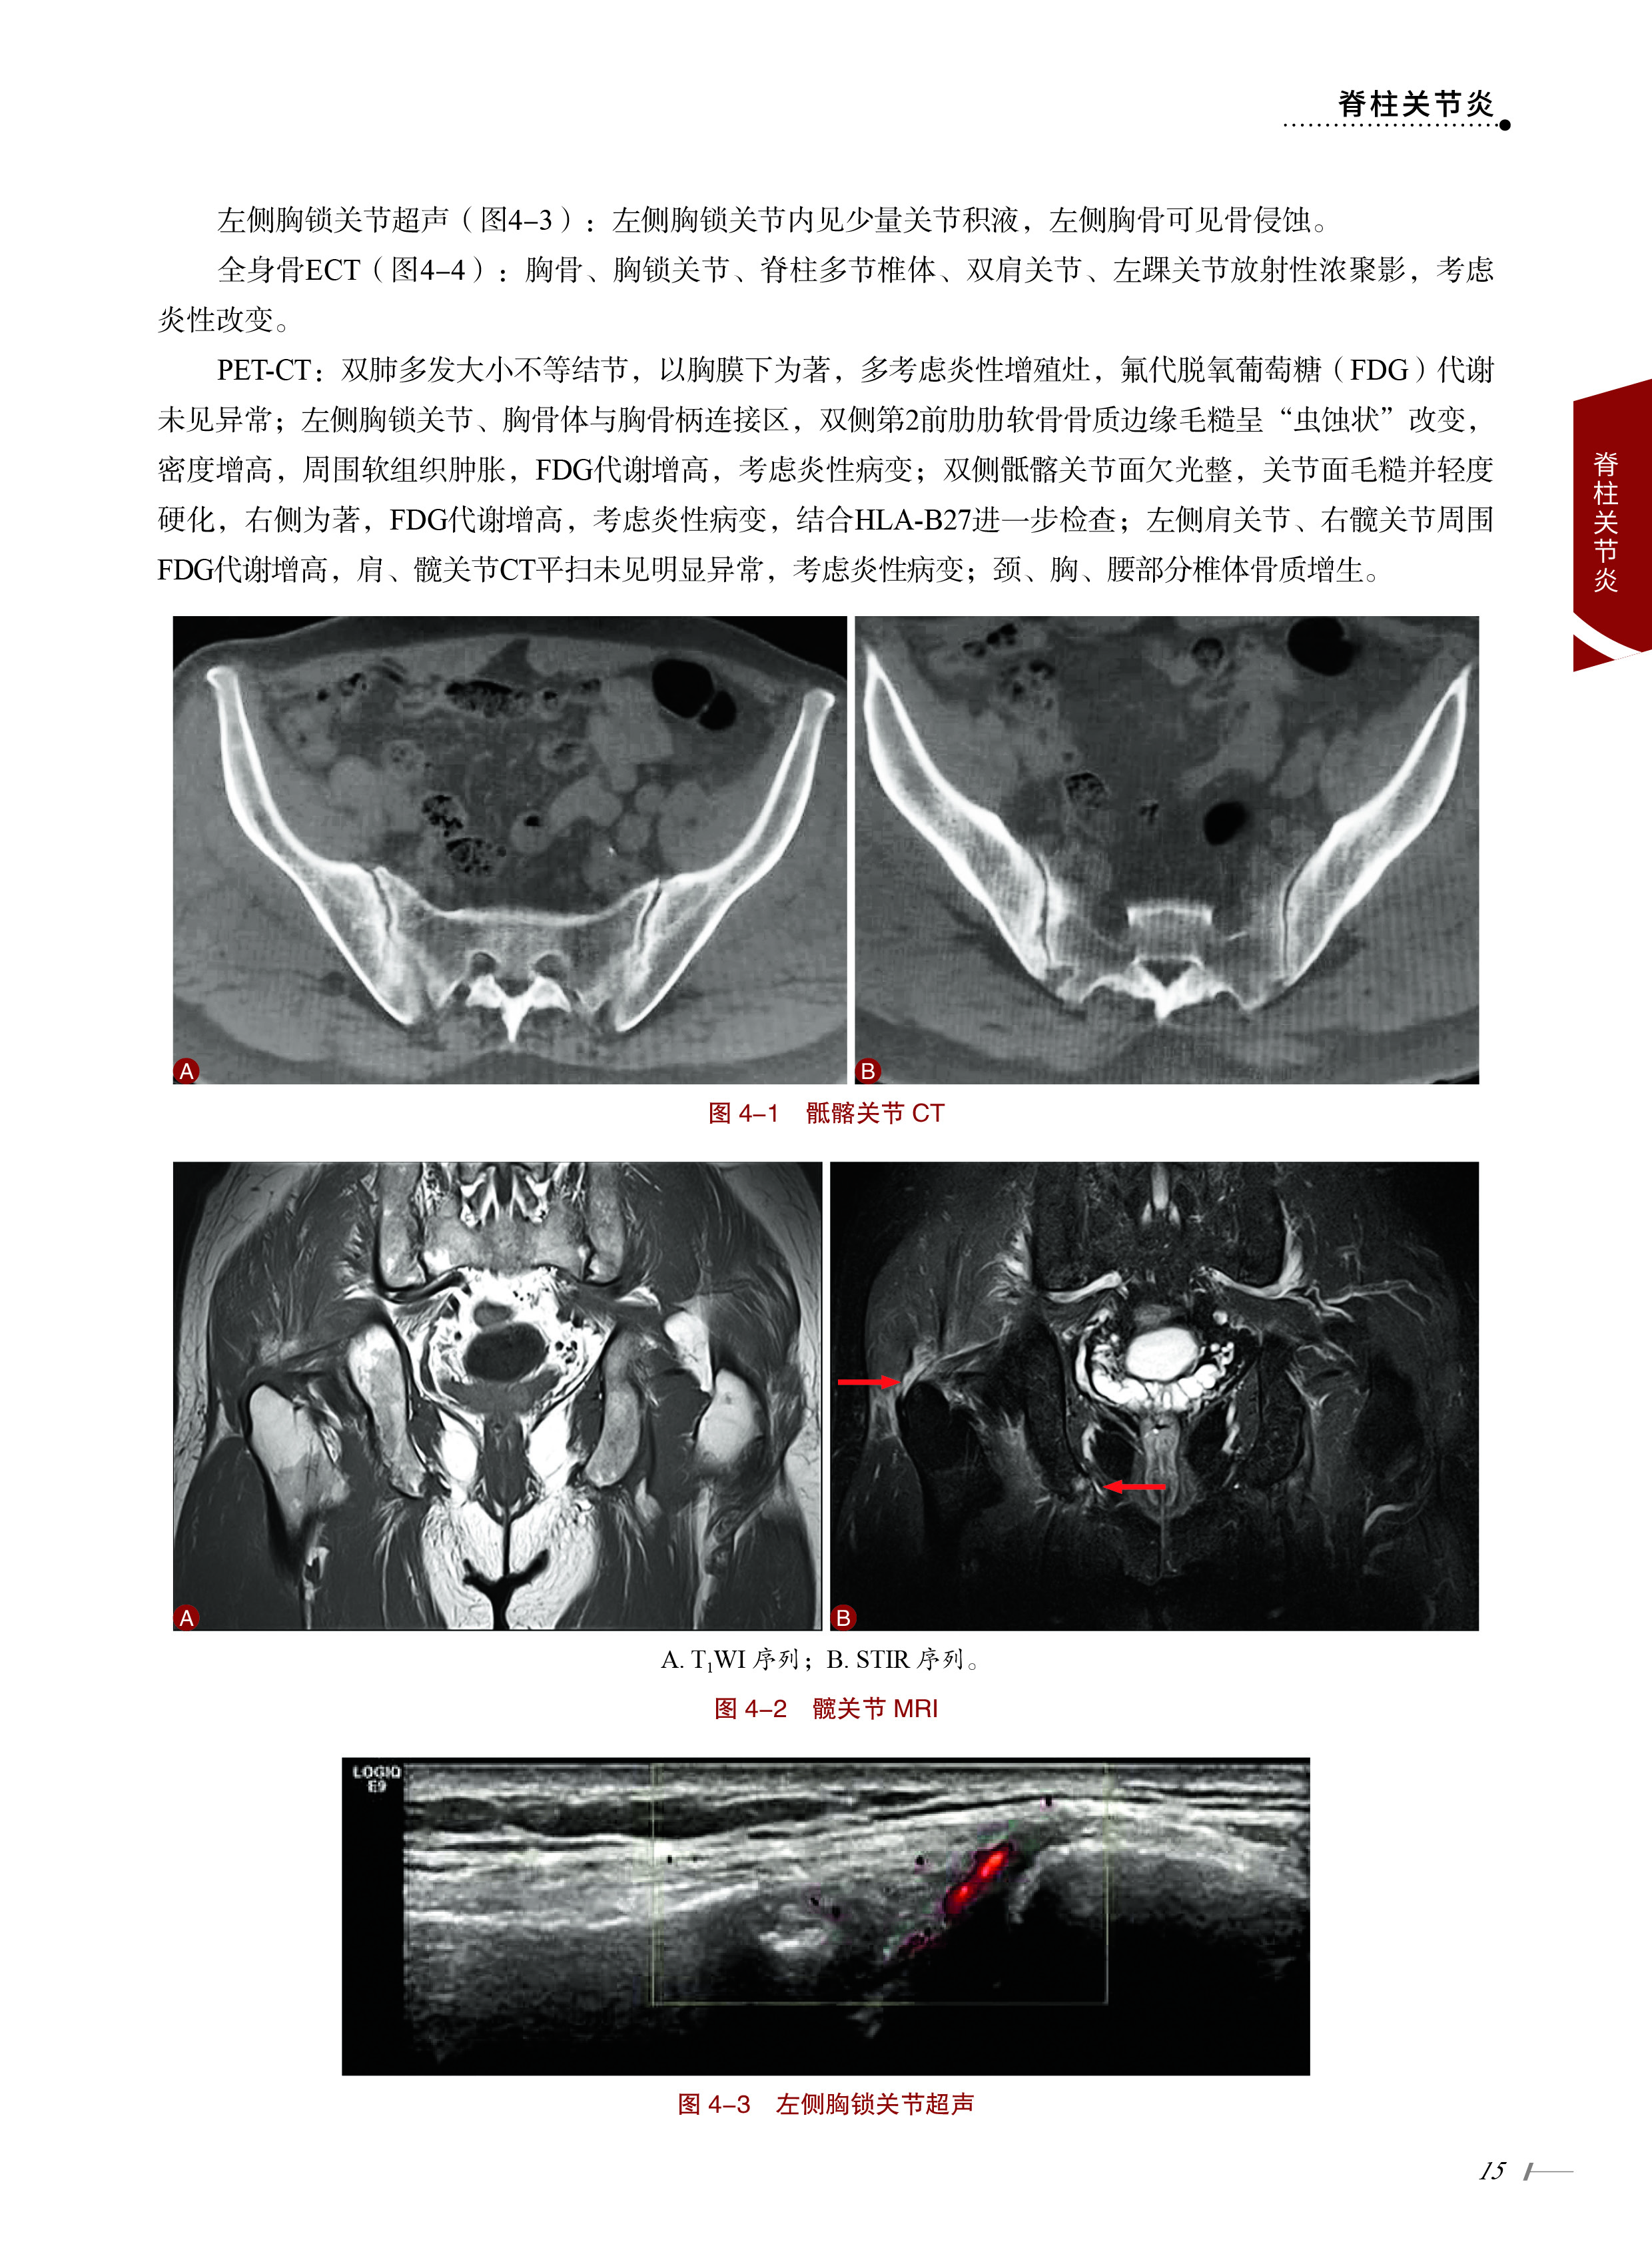

案例4 胸痛-发热-腰背痛-多关节肿痛 14